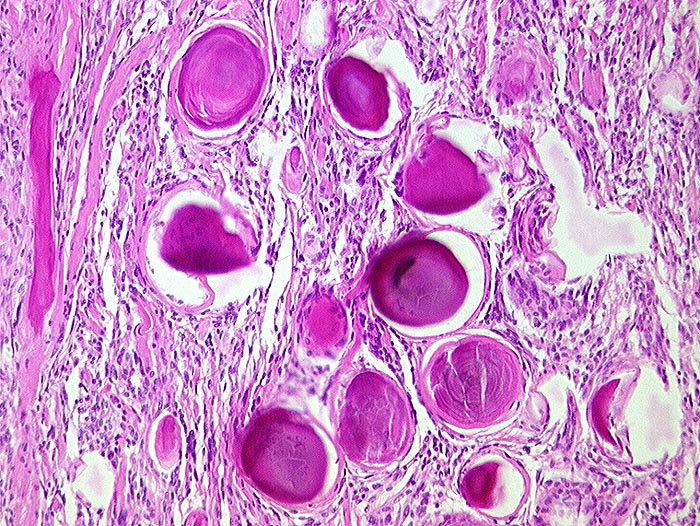

PathoPic ID 255 - Psammomatöses Meningeom

Psammomatöses Meningeom

benigner Tumor

Meningen

Nervensystem

Kugeliger Tumor im Bereich der Falx cerebri.

Histologie